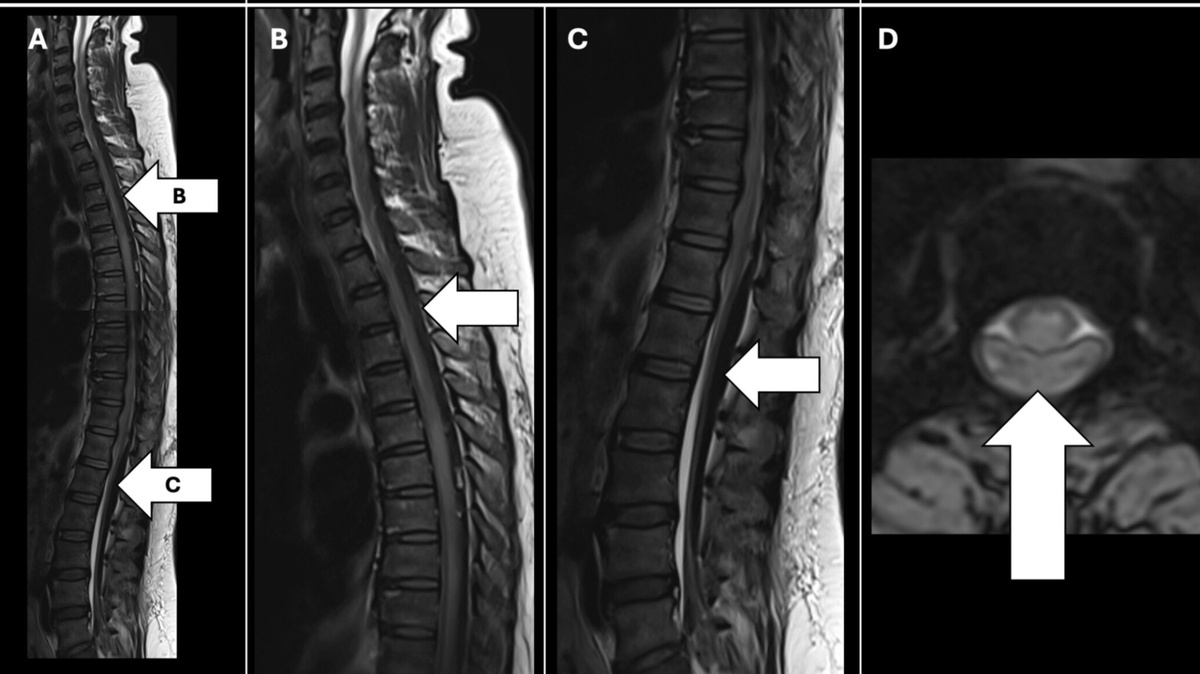

Как не пропустить метастазирование рака легкого в глазницу, необычная причина боли в шее и первое сообщение об острой кишечной

непроходимости из-за метастазирования комбинированного рака легкого — самые интересные клинические случаи прошедшего месяца. Подробнее: https://clck.ru/3SKoXF

Как не пропустить метастазирование рака легкого в глазницу, необычная причина боли в шее и первое сообщение об острой кишечной непроходимости из-за метастазирования комбинированного рака легкого — самые интересные клинические случаи прошедшего месяца.